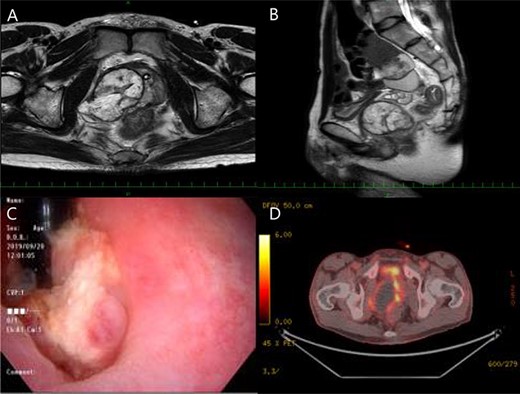

A 40-year-old man presented at a local hospital with urinary distention and was catheterized. Ultrasonography revealed a large prostatic mass; however, his prostate specific antigen (PSA) level was 0.62 ng/ml, which was within the normal range (<4.0 ng/ml). He was referred to our hospital for further examination and treatment. The patient had no pain, fever or abdominal distension. The results of a physical examination were normal and all other blood routine indexes were within normal limits. Other tumor markers, including CEA, CA19–9, CA-125, SCC and CYFRA, were also within normal limits. A digital rectal examination confirmed that the prostate was enlarged with perceptible nodules and a less clear border. Pelvic transabdominal ultrasound revealed an enlarged heterogeneous prostate mass. Magnetic resonance imaging (MRI) showed an enlarged, heterogeneous mass of 5.5 cm in the right prostate lobe (Fig. 1A and B). Vesical invasion was suspected by cystoscopy (Fig. 1C). In addition, positron emission tomography–computerized tomography and colonoscopy revealed rectal invasion of the tumor (Fig. 1D).

Magnetic resonance imaging (MRI) showed an enlarged, heterogeneous mass of 5.5 cm in the right prostate lobe (A, B), and vesical invasion was suspected by cystoscopy (C), besides positron emission tomography-computerized tomography and colonoscopy revealed rectal invasion of the tumor (D).